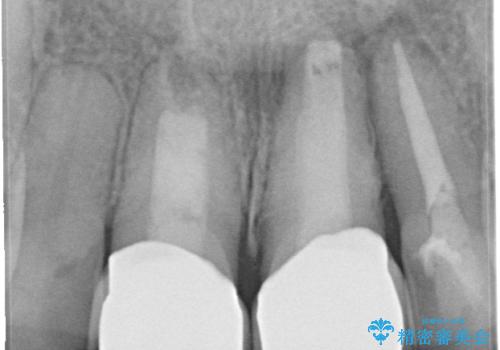

変色した前歯をセラミックできれいに レイヤリングセラミック

前歯のセラミック治療では、他の歯と色調をそろえるのが非常に難しいです。

他の歯に亀裂や白濁など複雑な色合いがある場合、それらをセラミックで再現することも可能ですが、スタンダードのオールセラミックではある程度の同調となります。

かぶせ物の種類: PFZ standard